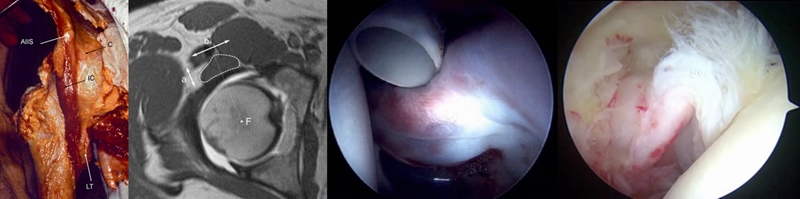

‌‌‌‌前关节囊除了进行X线指标的测量之外,我们尤其关注了厚度,测量方法选择在斜矢状位上,在整个前关节囊的‌‌中段进行了厚度的测量。见图9C中红色线段部位。

同时,也通过关节镜下进行了评估和测量。采用关节囊纵切的方式,就有机会测量到关节囊中段的厚度‌。通过镜下测量发现,BDDH组和FAI组‌‌的中位值分别是6mm和7mm。